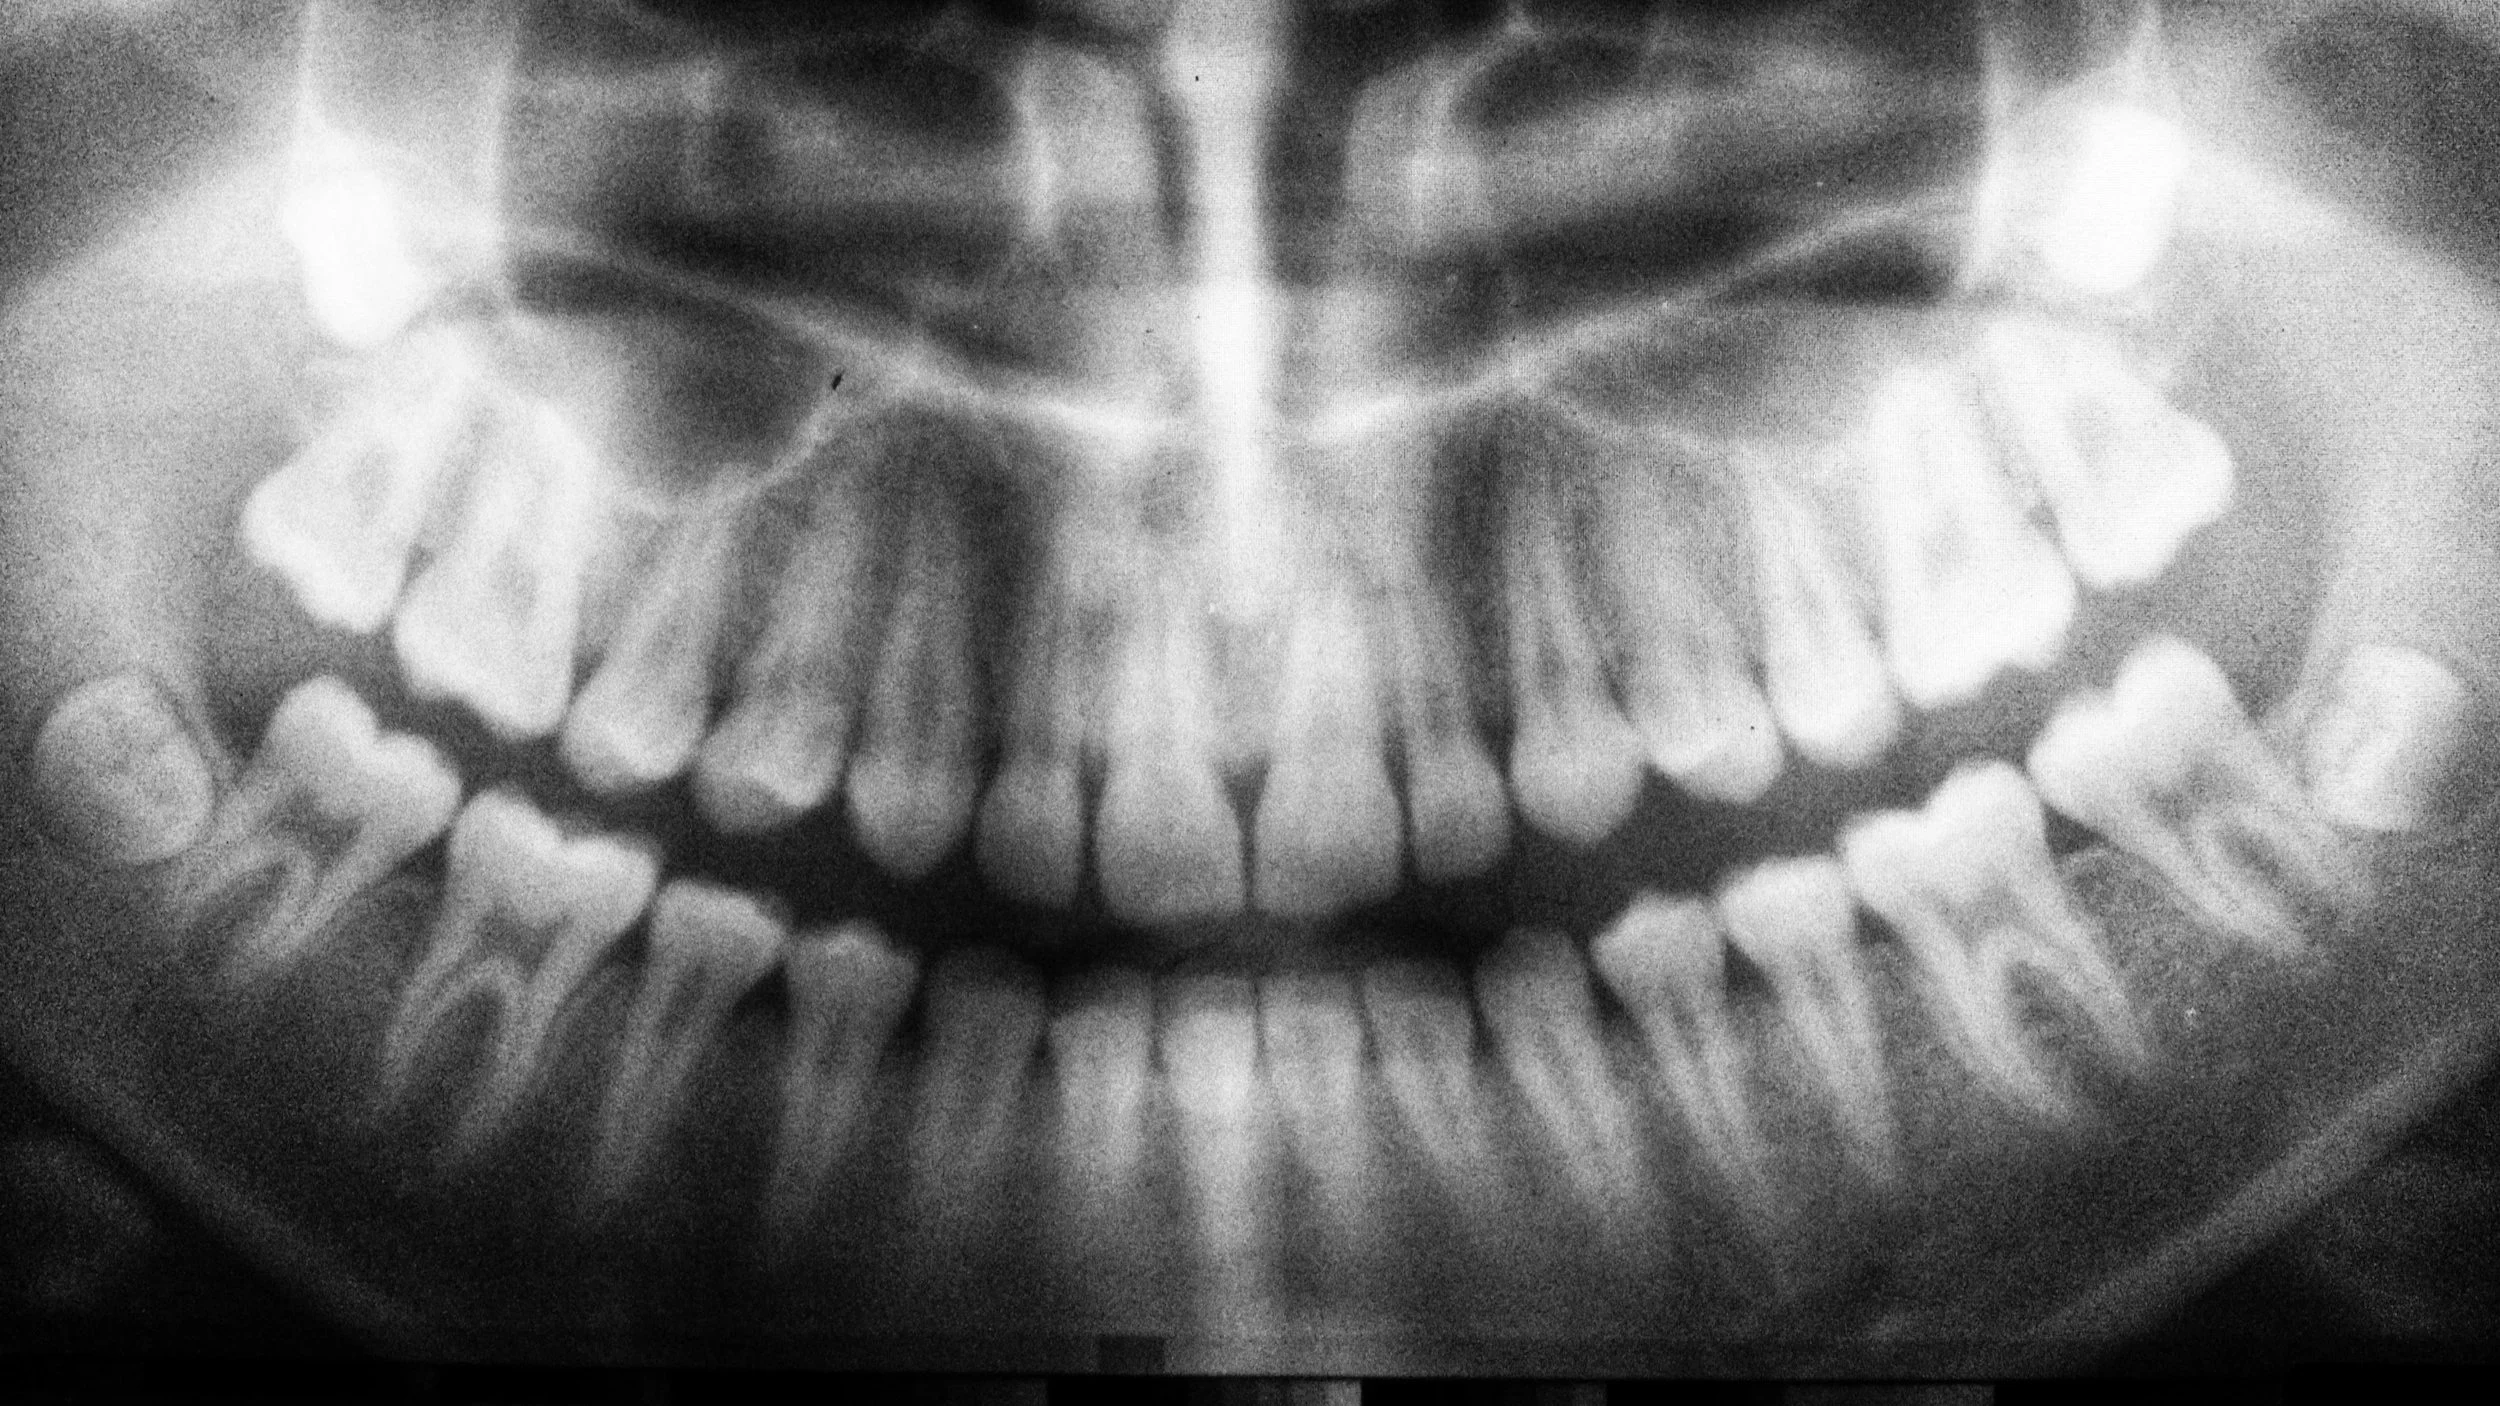

A black and white dental X-ray known as a panoramic view, showing a frontal view of upper and lower teeth and jaw as well as impacted wisdom teeth.

It is important for patients (teens and young adults especially) to periodically receive a thorough evaluation of wisdom tooth (third molar) development to be able to be advised of options regarding surgical removal versus continued monitoring. Sometimes 3D imaging is needed to determine the tooth’s relationship with adjacent anatomy, such as the inferior alveolar nerve or the sinuses. We would be happy to help you determine what treatment option is best for you. Dr. Matt served as an Exodontist in the U.S. Navy where he worked along side some of the Navy’s best oral surgeons, allowing him to receive exceptional training in the management of third molar extractions and their complications.